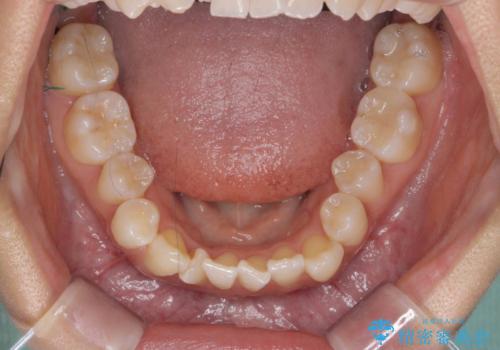

【審美装置】八重歯気になる

- 八重歯と叢生を主訴に来院されました。なるべく健康な歯を残したいという患者様の希望から、右側上下4番抜歯をしてワイヤー矯正する治療計画を立てました。

なるべく健康な歯を残したいという患者様の希望から、右側上下4番抜歯をして矯正しました。片側抜歯だったため、正中がズレないように気をつけながら治療を行いました。

正中もズレることなく主訴である八重歯と叢生を改善することができました。

患者様の満足度も高く治療を終えられました。